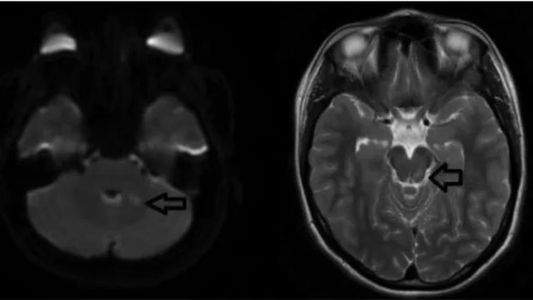

Después de insertar un catéter urinario, los médicos finalmente identificaron la fuente de su incontinencia: tenía un orificio entre la vejiga y la pared vaginal, conocido como fístula vesicovaginal en el lenguaje médico, que estaba causando que la orina se filtrara. Los médicos no tienen en claro si el desgarro fue causado por el propio corcho, pero el paciente fue "derivado a urólogos adultos para un diagnóstico y tratamiento adicionales".

La fístula vesicovaginal, como la que sufrió la joven de Serbia, puede tener graves consecuencias para la salud, como infecciones urinarias, dolor pélvico crónico y problemas en el parto. Además, puede tener un impacto emocional significativo en las mujeres, ya que la incontinencia urinaria puede ser una fuente de vergüenza y aislamiento social. Por esta razón, es importante recordar la importancia de buscar atención médica inmediata en caso de accidentes durante el sexo o cualquier otro tipo de actividad sexual.